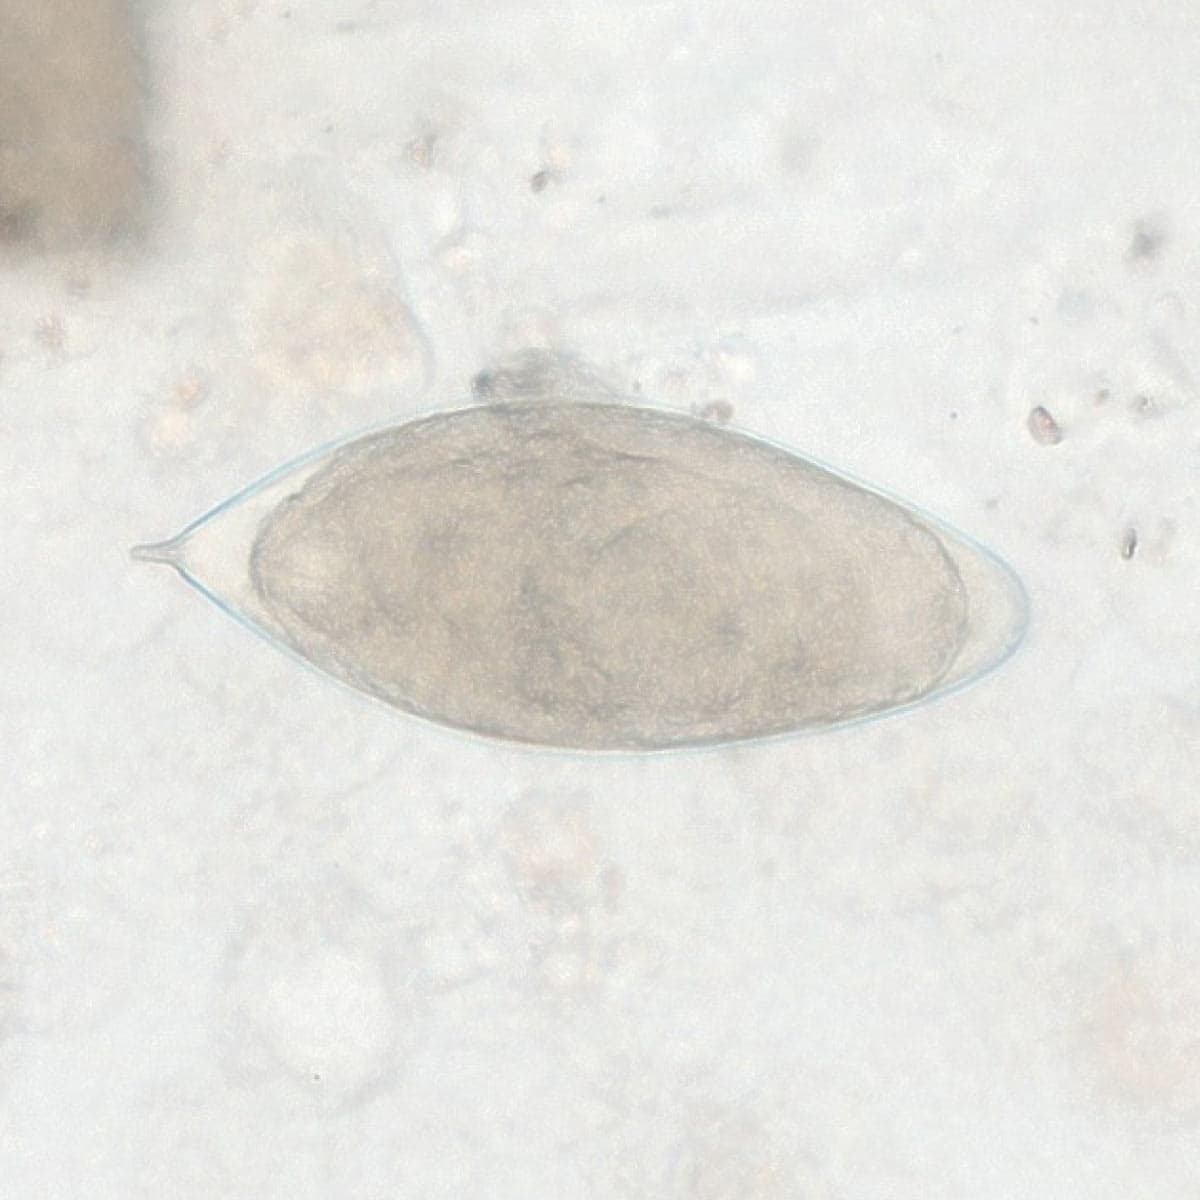

Automatic detection over 30 species

Built on worldwide parasite-positive specimens, ParaScout AI identifies a vast number of parasite species, including those that are clinically rare or challenging to find.

Evidence of results detection

Visual evidence is provided for every diagnosis.